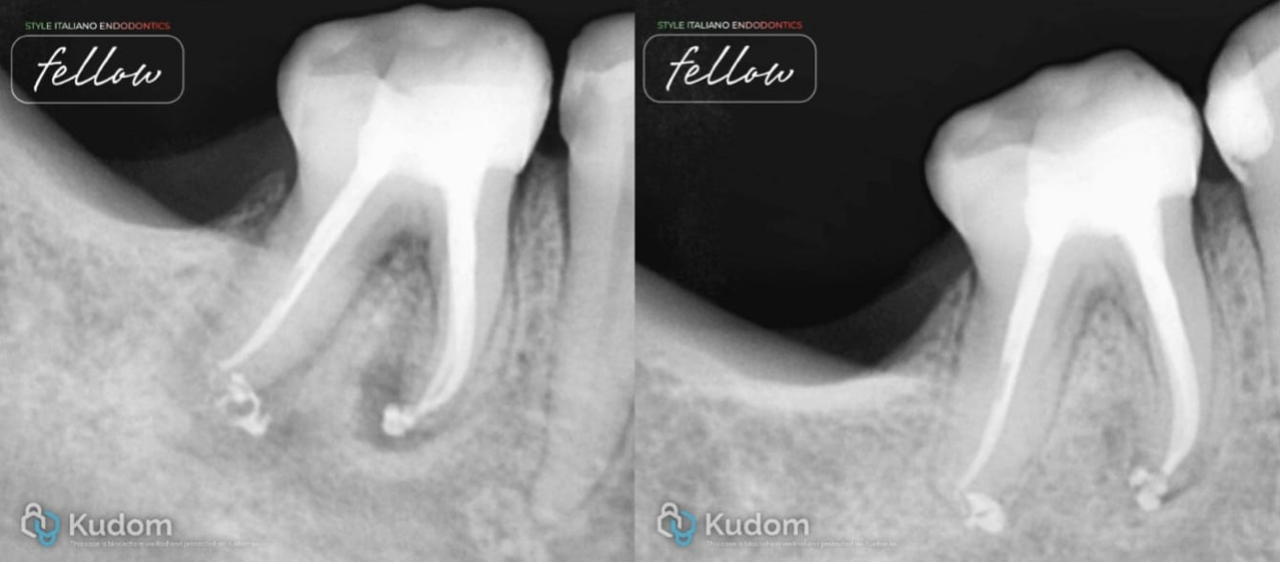

Advances in endodontic materials have influenced contemporary approaches to root canal obturation. A bioceramic sealers possess favorable properties, including biocompatibility, dimensional stability and the ability to form hydroxyapatite, which may enhance sealing root canal spaces. These characteristics have contributed to a shift toward simplified obturation techniques, particularly the single-cone approach. Compared with traditional compaction techniques, this method reduces procedural complexity and clinical time while maintaining an effective seal of the root canal system. For straightforward endodontic cases with adequate cleaning and shaping, simplified obturation protocols using bioceramic sealers have demonstrated predictable clinical outcomes.